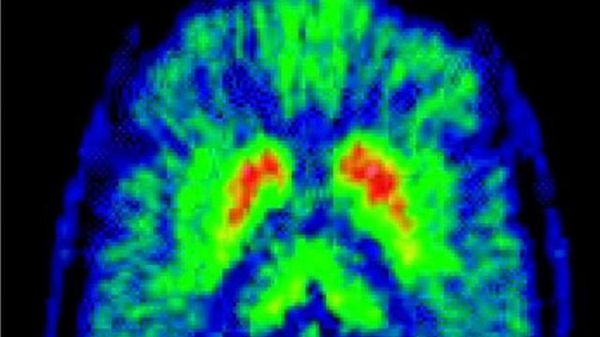

Notizie di Parkinson